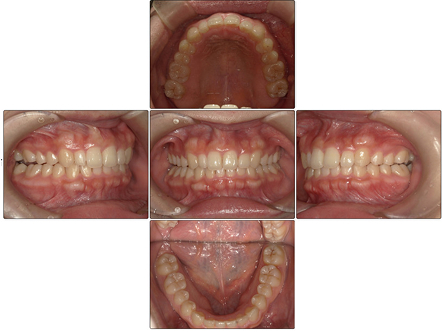

反対咬合を伴う下顎前歯叢生 【20代・女性】

お口の中全体の写真

Before

After

- 上下の歯列のガタツキは矯正治療前よりも改善され、上下の咬合関係も良好になりました。